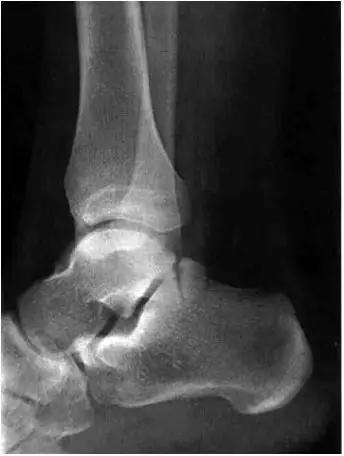

2、影像学表现:

- 踝关节正侧位X 线平片,侧位片均显示距骨后方有三角形或椭圆形的距后三角骨。部分病例伴有轻度的踝关节骨性关节病。

- MRI 检查示距后三角骨及周围软组织有水肿信号,距后三角骨和距骨之间正常的低信号纤维连接中断,出现液性信号。